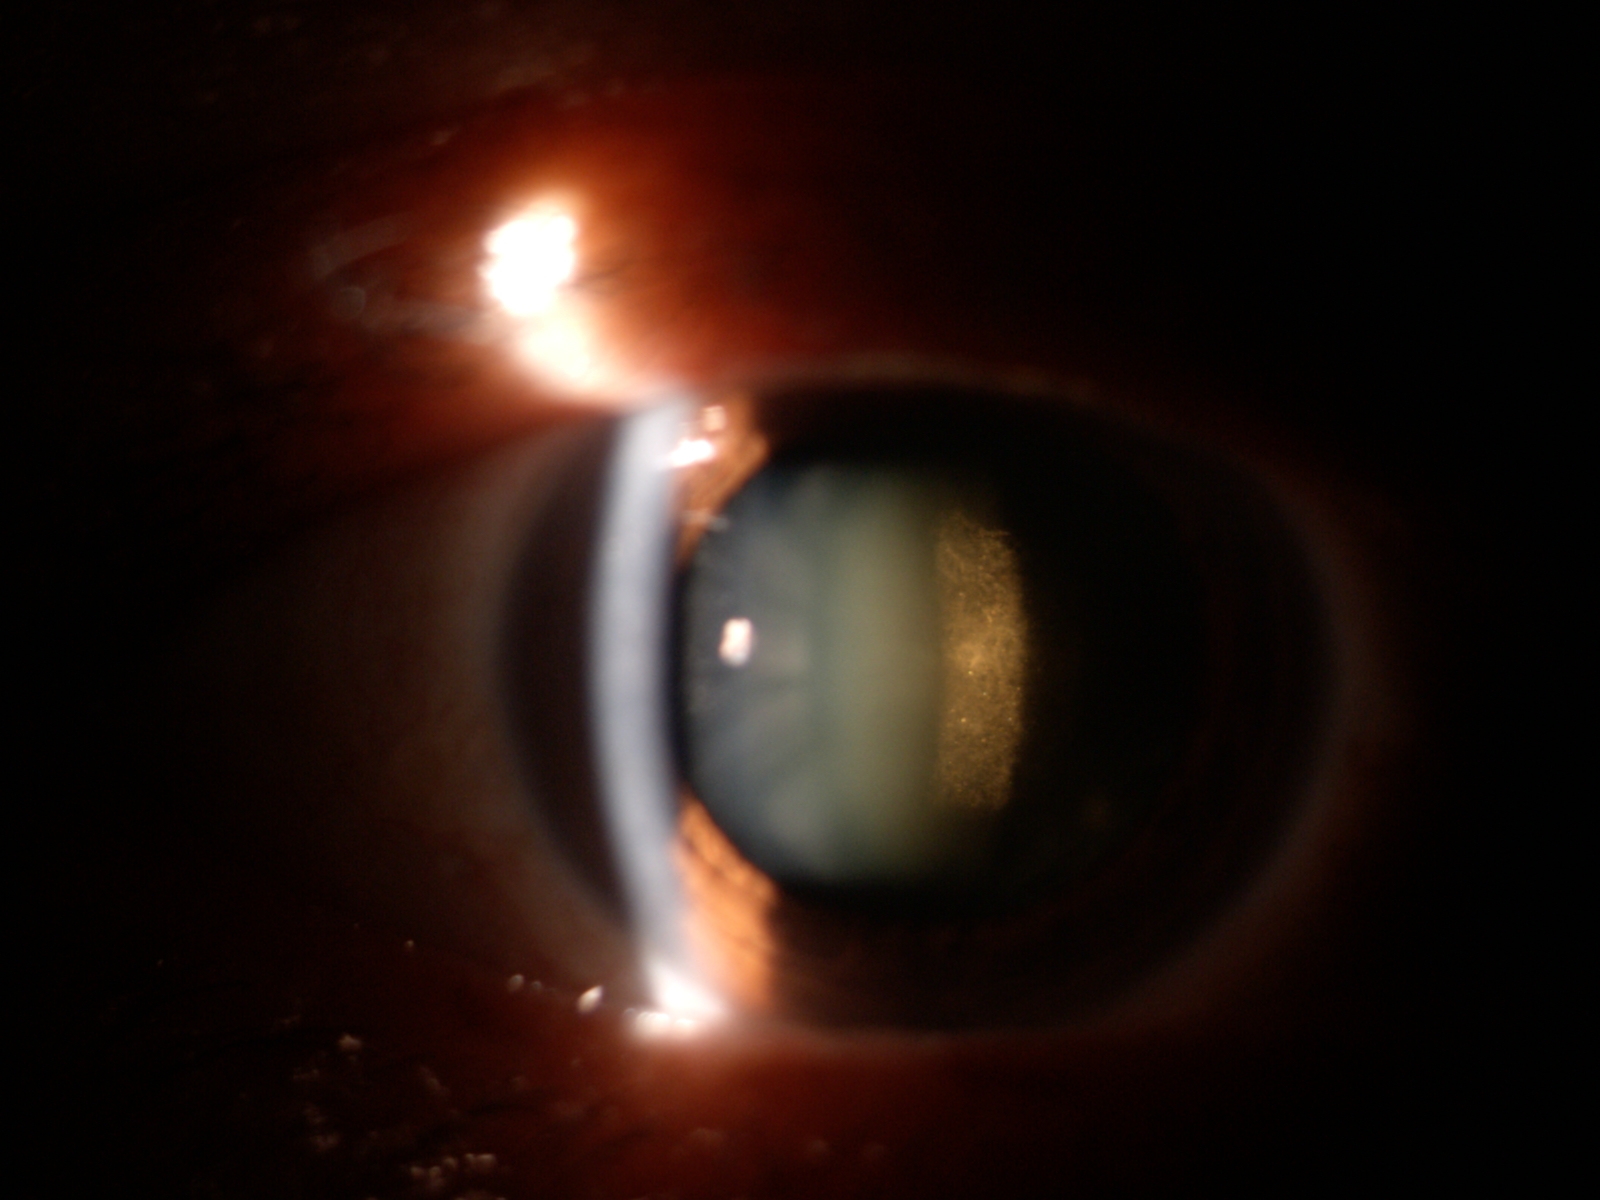

Katarak